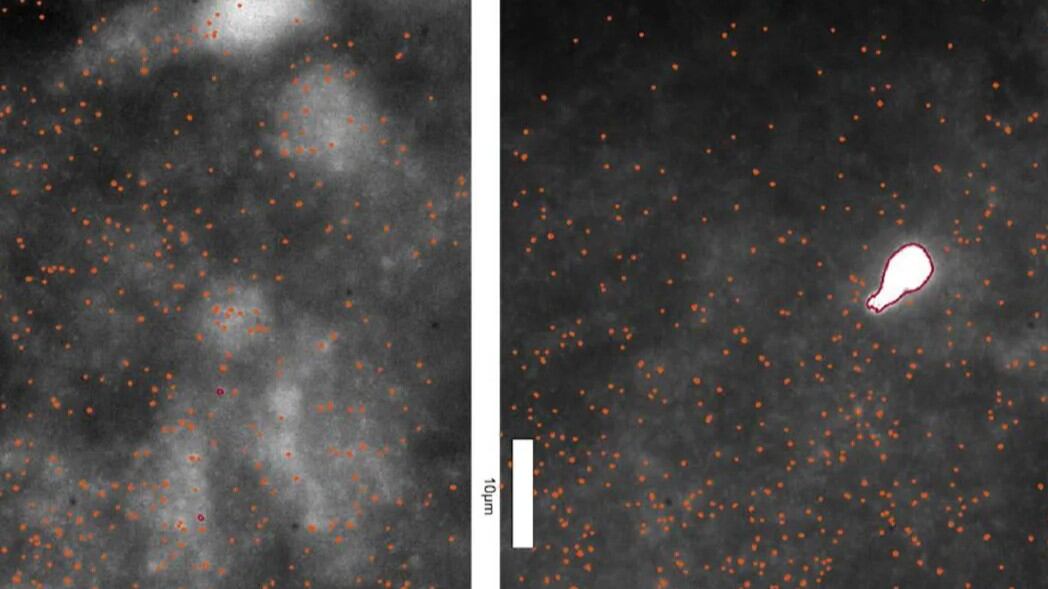

Os aglomerados, conhecidos como oligômeros de alfa-sinucleína, já eram vistos como um dos responsáveis pelo desenvolvimento do Parkinson, mas até então não tinham sido observados no tecido cerebral. A descoberta foi possível graças a uma nova técnica de imagem, que permite enxergar estruturas bilhões de vezes menores que um metro.

Os pesquisadores observaram que os oligômeros estão presentes em cérebros de pessoas com Parkinson e de indivíduos saudáveis. A diferença é que no primeiro caso, eles aparecem em maior quantidade, mais brilhantes e com dimensões maiores. A descoberta mostrou que o Parkinson começa a se desenvolver anos antes de os sintomas aparecerem.

“É a primeira vez que conseguimos observar oligômeros diretamente em tecido cerebral humano nessa escala: é como conseguir ver estrelas em plena luz do dia”, disse Rebecca Andrews, uma das autoras do estudo.